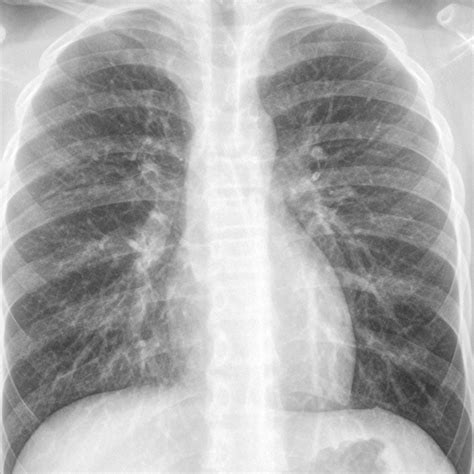

Healthy lungs appear mostly black on an X-ray because they are filled with air. When pneumonia is present, the areas of the lung affected by the infection appear as opaque, white, or cloudy patches. This phenomenon is known as consolidation. It occurs because the air in the alveoli has been displaced by fluid, inflammatory cells, or debris, which blocks the passage of X-rays.

• Bronchopneumonia: This presents as patchy, diffuse opacities scattered throughout both lungs, rather than being confined to one area.

• Interstitial Pneumonia: Often caused by viral infections, this shows up as fine, lace-like markings or reticular patterns rather than dense consolidation.